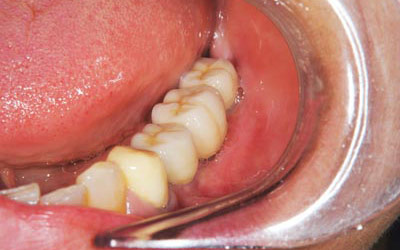

写真は、抜歯後の口腔内の写真です。見るからに、骨が少なく、陥凹してしまっていました。